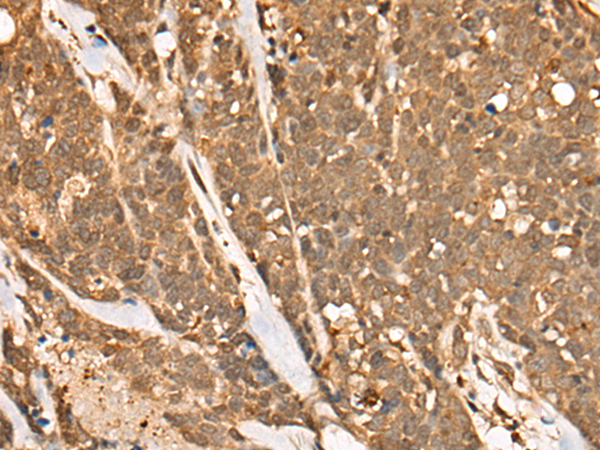

IHC positive control: |

Human esophagus cancer and human lung cancer |

IHC Recommend dilution: |

40-200 |